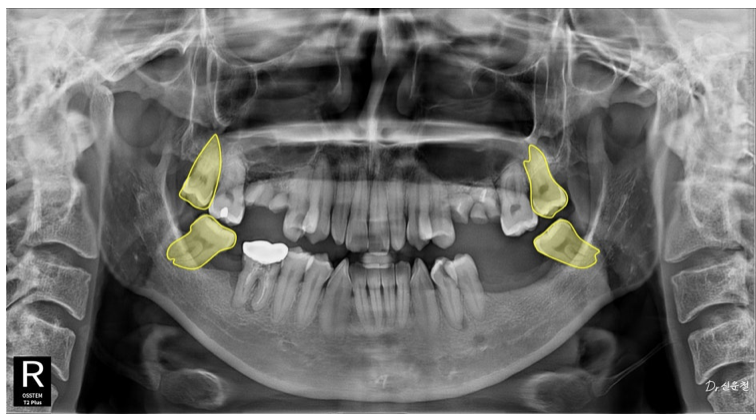

촬영일 250327

하지만 정밀 검진 결과, 깊게 진행된 사랑니 충치 뿌리만 남은 치아

잇몸뼈가 녹아 흔들리는 어금니 가 확인되었습니다.

통증이 없었던 것뿐,

문제는 이미 상당히 진행된 상태였습니다.

만약 웨딩 촬영 직전 증상이 악화됐다면

발치를 먼저 해야 하는 상황이었을 수 있습니다.